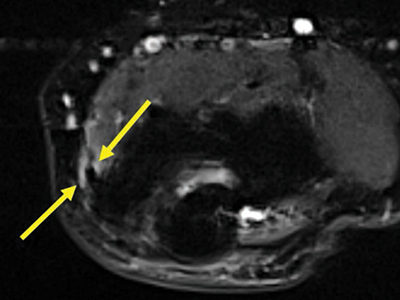

Figure 3

Axial fat-saturated T2-weighted image through the medial flexor origin with a peritendinous T2-hyperintense signal compared to muscle, score 1.

Multiple linear T2-hyperintensities were seen distally in the triceps tendon parallel to its fibers among all patients (Figure 2). The common flexor tendon showed signal alterations in 8% of patients; 4% of them had an increased signal around the tendon (score 1) (Figures 3) and 4 % of the patients had an increased signal within the tendon (score 2) (Figure 4).

The common flexor tendon was the tendon in which alterations of signal were most frequently observed (8%). Half of these abnormal signals occurred in the tendon itself, mimicking a tendinopathy, similar to the findings in the literature (3%) [11].